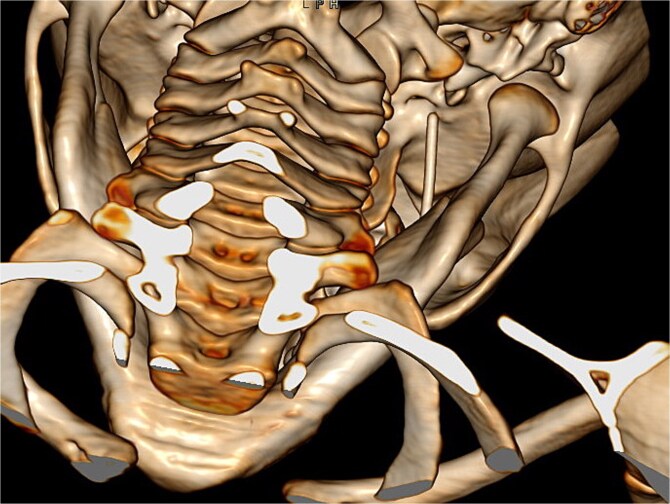

局部麻醉和神经阻滞是牙科治疗中常用的方法。虽然它们的并发症发生率较低,但局部事件如针头骨折可能导致危及生命的后果。我们提出一个病例针头骨折在一个4岁的女孩谁接受了一个小牙科手术。针通过卵圆孔向颅内移动。她需要一个多学科的管理和最后的神经外科干预,以去除它。除了初步诊断计算机断层扫描(CT)外,最重要的是获得术中成像工具(儿科人群最好是低辐射CT)来监测针移的潜在风险。该报告表明,除其他并发症外,断针可能向颅内移位,强调了在拥有适当设备和专家的三级转诊医院处理这些病例的重要性。

Local anaesthesia and nerve block are common practices in dental therapy. Although they are associated with low rate of complications, local events such as needle fracture could entail life threatening consequences. We present a case of a needle fracture in a 4 year old girl who underwent a minor dental procedure. The needle migrated intracranially through the foramen ovale. She required a multidisciplinary management with a final neurosurgical intervention in order to remove it. In addition to an initial diagnostic computerized tomography (CT), it was of utmost importance to have access to an intraoperative imaging tools (preferably low radiation CT in paediatric population) to monitor the potential risk of needle migration. This report demonstrates that a broken needle may migrate intracranially, among other complications, underscoring the importance of managing these cases in a tertiary referral hospital with the appropriate equipment and specialists.